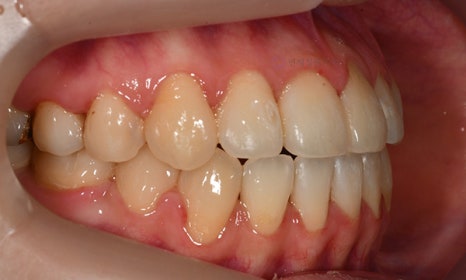

다음 케이스 역시 위 아래 치아의 중심선 차이가 있으며, 덧니 및 반대교합이 관찰되었습니다. 위 치아의 중심선도 얼굴의 중심선과 일치하지 않고 우측(사진 상 왼쪽)으로 틀어져 있었습니다. 본 환자는 발치를 하지 않고 치아를 뒤로 이동시켜서 치아의 중심선도 맞추고 얼굴의 중심선과도 맞추었습니다.

2020.1

교정 마무리 후 위 치아의 중심선은 얼굴의 중심선과 일치하였으며, 위 아래 치아의 중심선도 일치하였습니다.